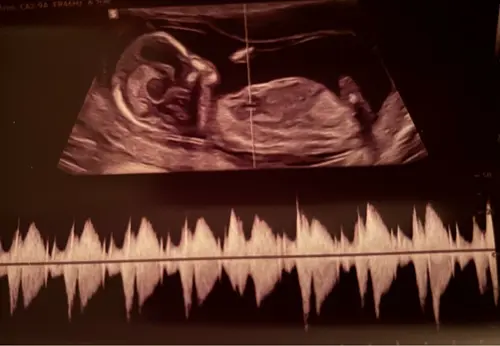

Ik zelf zie hem ook niet echt maar ook te weinig verstand van ik zal nog eens een andere erbij zetten van dezelfde echo

Oeh lastig, ik zie wel een nub maar vind het lastig om te zien of deze nu meer in een driehoek staat tov de ruggengraat of dat het recht door loopt 😅. Misschien zijn er kenners die het zien?